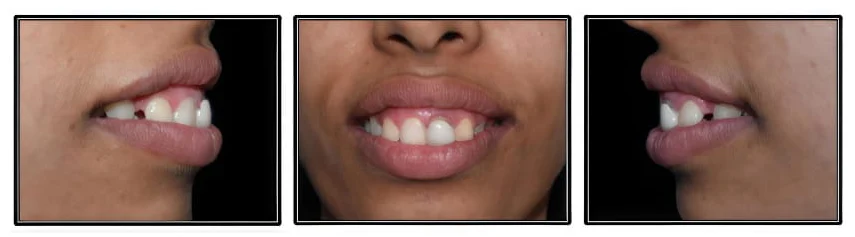

Smile Designing

Injecting art into dentistry

Re-Discover Your Smile

Smile Design with Ceramic Veneers